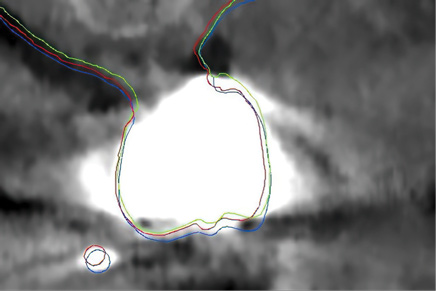

Fig 14. Close-up view at the level of the maxillary right first molar shown in Fig 12 with the outlines of the registered STL stone models to the CBCT anatomy, using various methods. Green outline: automatic registration plus manual fine-tuning, no scanning appliance. Red outline: landmark registration using a scanning appliance that was CBCT scanned; in this case the STL file of the model teeth was first produced by DICOM to STL conversion, and the registration to the CBCT anatomy followed. Blue outline: landmark registration using a scanning appliance that was CBCT scanned; in this case the registration was accomplished based on the voxels of the glass beads of the scanning appliance, and then the STL file of the stone model was produced. Differences of up to 1 mm can be noted among the three methods.

Figure 14

Fig 15. Differences in the registration outcome of the stone model among the three different methods described in Fig 14 were calculated with a metrology software. The mean absolute difference was 0.618 mm, but the signed differences ranged from -2.1 mm to 5.6 mm.

Figure 15